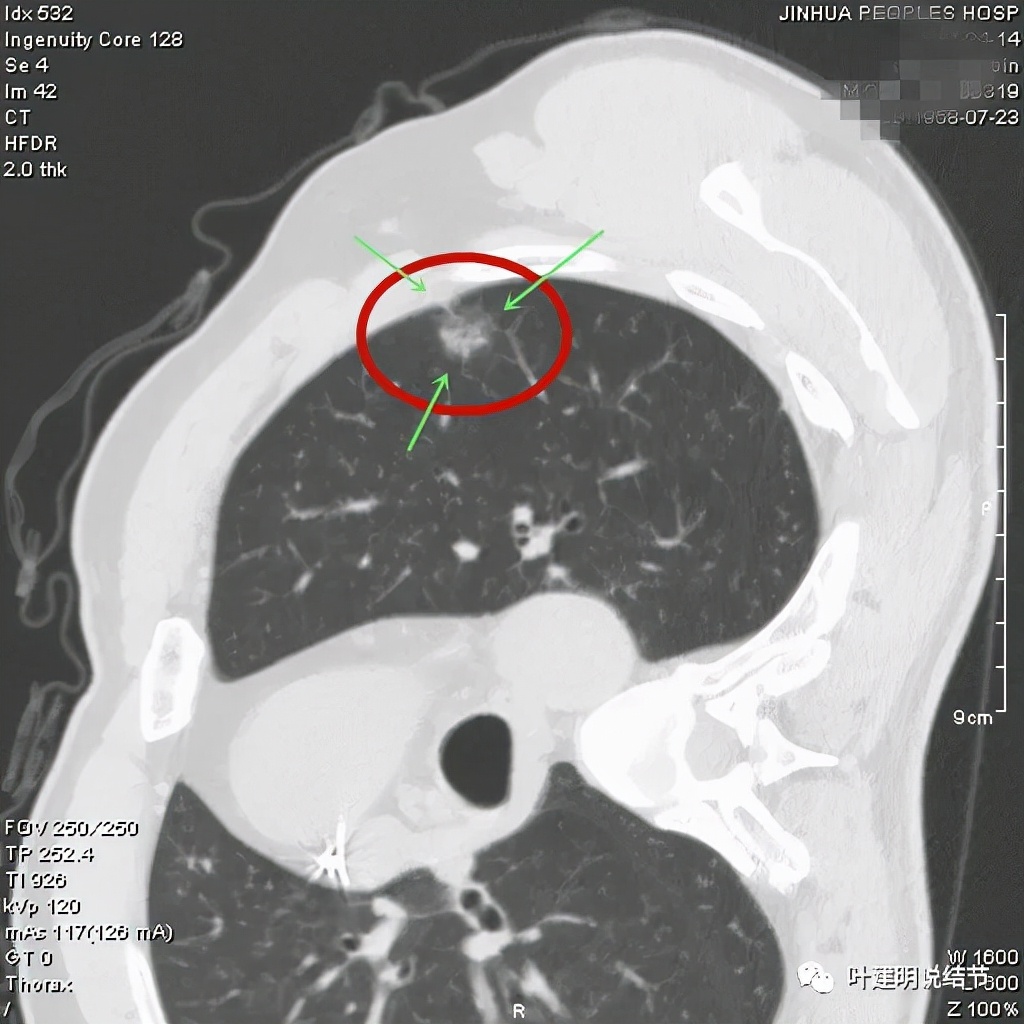

病灶密度较低,膨胀性略,瘤肺边界在靶扫描上还是显得有些清晰的

病灶瘤肺边界清,密度偏低,有点散,但有微小血管进入(桔色箭头)

病灶整体密度较低,但轮廓较清,内部密度不大均匀,显得杂乱

不均质的偏低密度磨玻璃结节,轮廓清

从以上靶扫描图像上看,给人的印象是肿瘤范畴的结节,是混合磨玻璃结节,但磨玻璃部分的密度偏低,有的边缘显模糊,中间有点状高密度,也有微小血管进入,应该至少微浸润性腺癌可能性大。持续存在已经2月余,位置又还靠边上的,可考虑手术切除。下面再来瞧瞧后处理重建的图像: